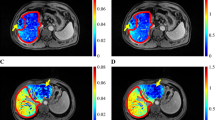

Representative CT imaging of a cholangiocarcinoma in the a arterial and b portal venous phases. c CT volumetry of the liver was performed to calculate FRLV and sFRLV. d Three-dimensional segmentation of the liver (without the tumor) and the spleen as well as ROI placement in the L1 vertebra for radiomics analysis was performed by two experienced radiologists in the portal venous phase of baseline CT. e–h Representative peri-interventional fluoroscopic images of a portal and hepatic vein embolization. CT Computed tomography, FRLV Future remnant liver volume, sFRLV Standardized future remnant liver volume, ROI Region of interest

Image Segmentation and Feature Extraction

Two experienced radiologists, blinded for clinical and interventional data, reviewed the baseline contrast-enhanced CT images of the abdomen. The readers chose liver and spleen parenchyma as well as bone marrow, with these being defined as possible influencing factors for liver hypertrophy after PVE. Thereafter, the readers independently segmented the entire liver (without tumor) and spleen volume, as well as a 1 cm3 volume-of-interest (VOI) of the first lumbar vertebral bone marrow, each as a separate label map. Liver-, splenic-, and bone marrow-specific radiomic features from labeled CT data were extracted twice, each by the same independent readers, for interobserver analysis, and included 162 first-order logic features and 216 grey level co-occurrence matrix (GLCM) features. These features are used to quantify shape (e.g., compactness, sphericity), intensity (e.g., histogram statistics of the mean, standard deviation, and median), and texture matrices, including the GLCM, where the differences represent the heterogeneity of the tissue. Image analysis and feature extraction was performed by using a freely available software package (3D slicer, version 4.11.2).